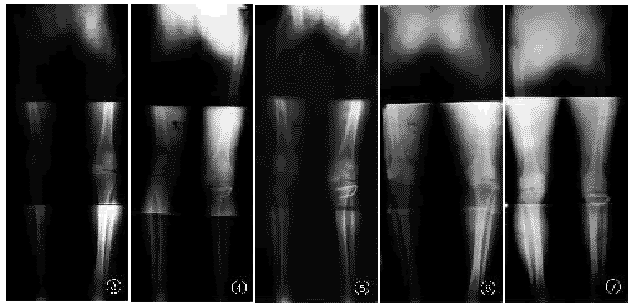

术前下肢立位力线均呈明显内翻排列,而术后各阶段下肢立位力线均呈轻度外翻排列,下肢立位力线在182°~185°间远期效果最好(表2),分析术后下肢立位X线片发现,术后2~5年内下肢力线基本维持不变,术后2~5年内侧股胫关节间隙都有不同程度增宽,但立位X线片示均未超过1.5mm,外侧股胫关节间隙亦未见明显退变加重现象。5~9年组,下肢立位力线在182°~185°间者,内外侧股胫关节间隙与术前相比均无退变加重现象(图3~7),髌股关节亦无明显变化。适当的下肢力线能延缓膝关节的退变进程。

图3 术前下肢力线呈内翻排列,左内侧间隙明显变窄,外侧间隙相对正常 图4 术后4年10个月,下肢力线183.5°,退变征象无明显加重 图5 术后8年2个月,下肢立位力线与图4大致相仿,说明下肢力线矫正后退变延缓 图6 术前左下肢位力位力线明显内翻排列,内侧间隙明显变窄,外侧间隙相对正常 图7 术后6年3个月,左内侧间隙增宽,外侧间隙无明显变化